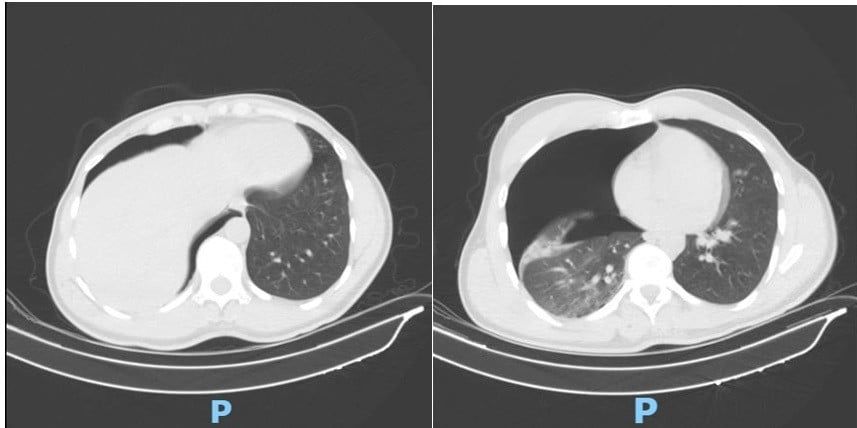

Ngay khi nhập viện, người bệnh được thực hiện CT scan lồng ngực – mạch máu khẩn cấp, ghi nhận:

- Tràn khí màng phổi phải lượng nhiều, chèn ép phổi gây khó thở

Hình 1. Phim CT scan lồng ngực sáng ngày nhập viện ghi nhận tràn khí màng phổi phải lượng nhiều

Trước nguy cơ suy hô hấp tiến triển, vào 5 giờ sáng cùng ngày, ê-kíp Khoa Phẫu thuật Tim – Lồng ngực – Mạch máu đã khẩn trương tiến hành phẫu thuật đặt dẫn lưu màng phổi phải cấp cứu do TS.BS Đồng Đức Hưng trực tiếp thực hiện. Thủ thuật được tiến hành nhanh chóng, chính xác, giúp phổi nở lại tốt, cải thiện rõ rệt tình trạng hô hấp của người bệnh chỉ sau vài giờ.